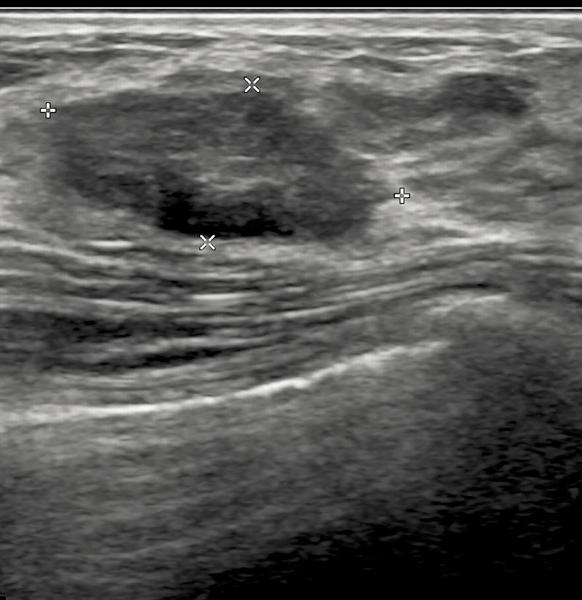

As a Consultant Radiologist with more than 35 years of experience, I provide specialist ultrasound imaging designed to investigate lumps, bumps, injuries and even detect foreign bodies under the skin. Many patients present with cystic lesions, such as ganglions or bursitis, and with this advanced imaging, I am able to confidently tell the difference between these and solid growths, such as lipomas. Ultrasound is also good for assessing more sinister solid lesions and guide further management.

Ultrasound is effective for evaluating cysts, solid tumours, ganglions, hand, wrist, and salivary gland lumps, helping to guide further steps if needed. - Accessible Private Ultrasound in Leicester

They can detect lipomas, cysts, ganglions, bursitis, injuries, foreign bodies, and help guide further investigations if needed.